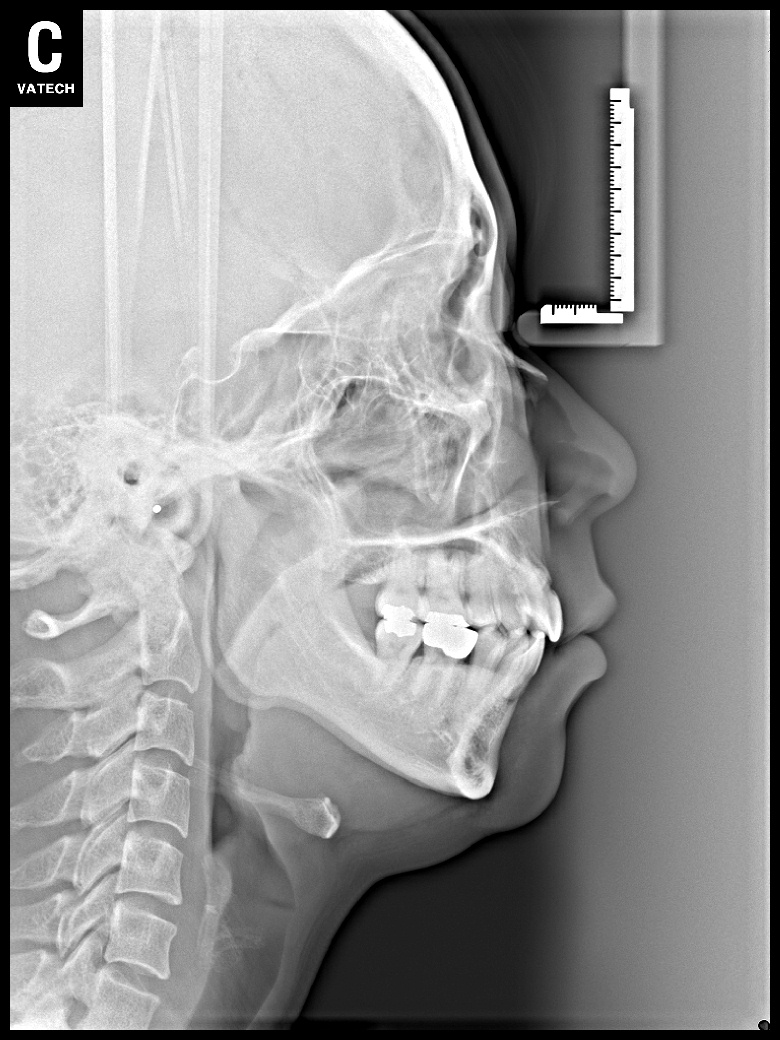

치료 후 사진입니다.